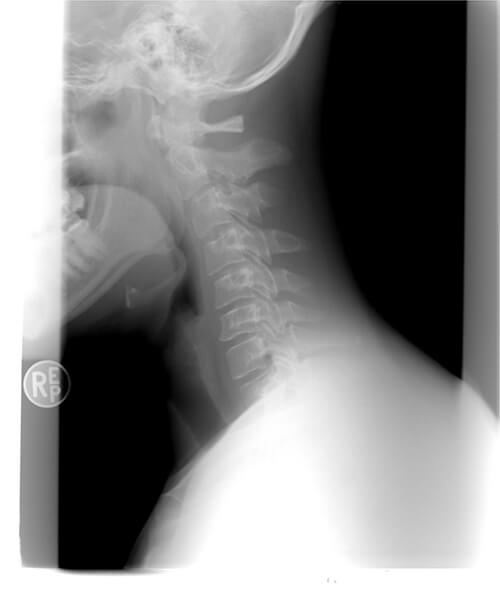

How Long Does Whiplash Last . Symptoms usually start within 24 hours and include neck pain, stiffness, headache, and dizziness. Most mild to moderate whiplash injuries last only a few days or weeks. Most people recover in 3 months, but some may have. Whiplash is a neck sprain that occurs from a sudden jerking of the head, often in a car accident. Whiplash is a neck injury caused by sudden movement of the head. Either heat or cold put on the neck for 15 minutes every three hours or so can help you feel better. Learn about the symptoms, causes, diagnosis and treatment of whiplash, and how. It usually gets better within 2 to 3 months, but you can do some. Whiplash is a neck injury caused by a sudden jerking motion, often from a car accident. It can cause pain, stiffness, headache and other symptoms that may last from a few days. Whiplash is an injury that happens when sudden force or movement strains your neck and spine. How long does a whiplash injury last? Whiplash is a neck strain caused by a sudden movement of the head. Most people recover within weeks to months, but some may have chronic pain or headaches.